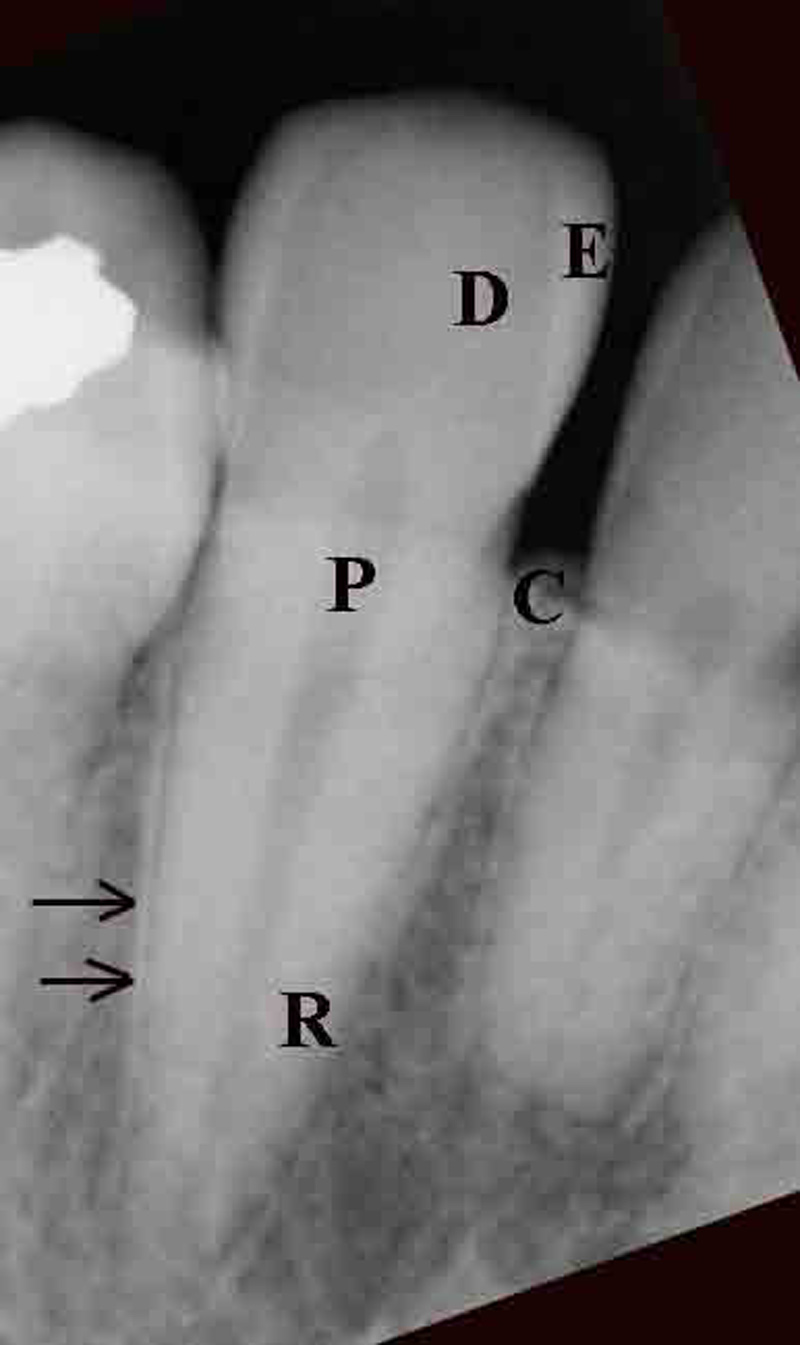

A thorough knowledge of tooth anatomy is important for proper diagnosis of dental disease and for recognition of dental apparatus. Each tooth contains distinct layers visible on conventional radiographs (figure: tooth anatomy). The anatomic crown is the portion of the tooth that is covered by enamel. Enamel, formed from ameloblasts, is the most dense tissue in the human body, composed of 97% inorganic salts. Enamel appears as the most radiopaque layer of the tooth on conventional radiographs.

The layer deep to the enamel, dentin, is a calcified, porous tissue, the second most dense tissue in the body. Dentin, laid down by odontoblasts, is a comprised of 65% inorganic salts, and forms the bulk of the tooth. Dentine is less dense than enamel, and appears as a gray opacity on conventional radiographs (figure: tooth anatomy). Dentin surrounds the pulp chamber, which lies deep within the anatomical crown, and the pulp, or root canals within the root of the tooth. Pulp consists of connective tissue, nerves, lymph channels, and blood vessels and is visualized as a radiolucency generally in the center of the anatomical crown and root extending to the apex. Reserve odontoblasts embedded within the lacunae of the dentin lay down secondary, or reparative dentin and reduce the pulp cavity and root canal size with age.

The tooth root is the elongated internal structure of the tooth and begins where the enamel covering ends. This junction is called the cemento-enamel junction (CEJ). The alveolar bone socket begins approximately 1.8 mm from the CEJ. The non-covered root distance is called the biologic width and is required for gingival, or epithelial attachment. Alveolar bone surrounds the roots and supports the tooth. If a tooth is extracted, the alveolar bone will in time be resorbed. Pathological processes, such as periodontal disease, can remove alveolar bone as well. Alveolar bone loss should be suspected when the distance from the alveolar ridge to the cemento-enamel junction of the supported tooth is greater than 1.8 mm, or when the opacity of the alveolar crest is lost. Below the alveolar bone is basal bone. The transition between the two is not radiographically visible.

In an individual with either advanced, chronic, or refractive periodontal disease alveolar bone may be completely lost leaving only the residual basal bone. The wall of the alveolar socket, or lamina dura, is made of dense cortical bone. It appears on a radiograph as a white line next to the dark line of the periodontal ligament space. The periodontal ligament space, containing the periodontal ligament, is visualized between the lamina dura and the tooth root as a radiolucent line.

The periodontal ligament is comprised of radiolucent collagen bundles and functions to stabilize the teeth within their sockets. Its appearance varies from tooth to tooth, depending upon the overall periodontal health. It generally has a thin radiolucent appearance from the CEJ to the root apex. Endodontic or dental pulp pathology shows as a widened radiolucency within the periapical region that may extend toward the top of the tooth but narrows as it goes superiorly. Periodontal pathology, on the other hand, shows as an ever widening radiolucency from the tooth root toward the CEJ and the top of the tooth.

Cementum is a bone like substance forming the thin surface layer over the tooth roots. It functions as an anchor point for the attachment of periodontal ligaments. Cementum on the root surface is nearly the same density as the dentin, thus it is usually not visible radiographically.

| E - enamel; D - dentine; P - root pulp; R - tooth root; arrows - lamina dura |